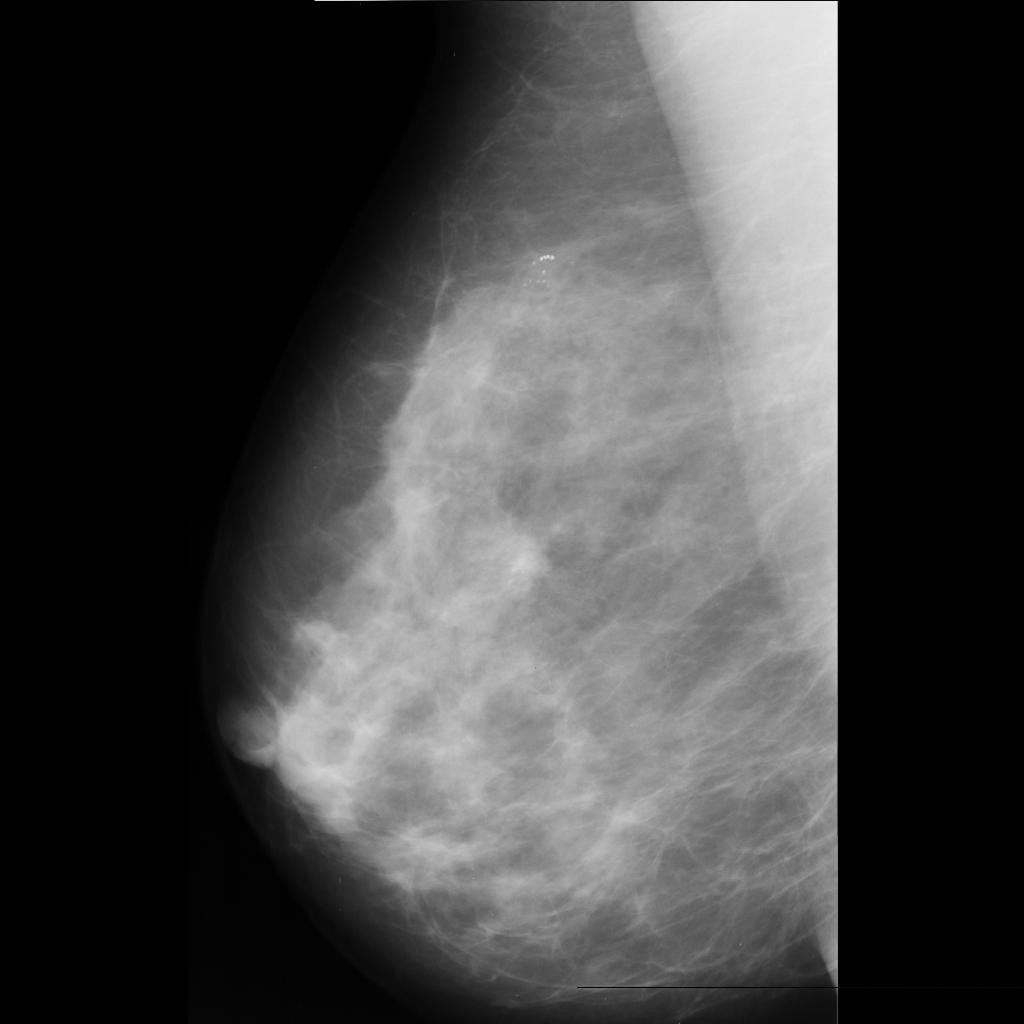

malignant